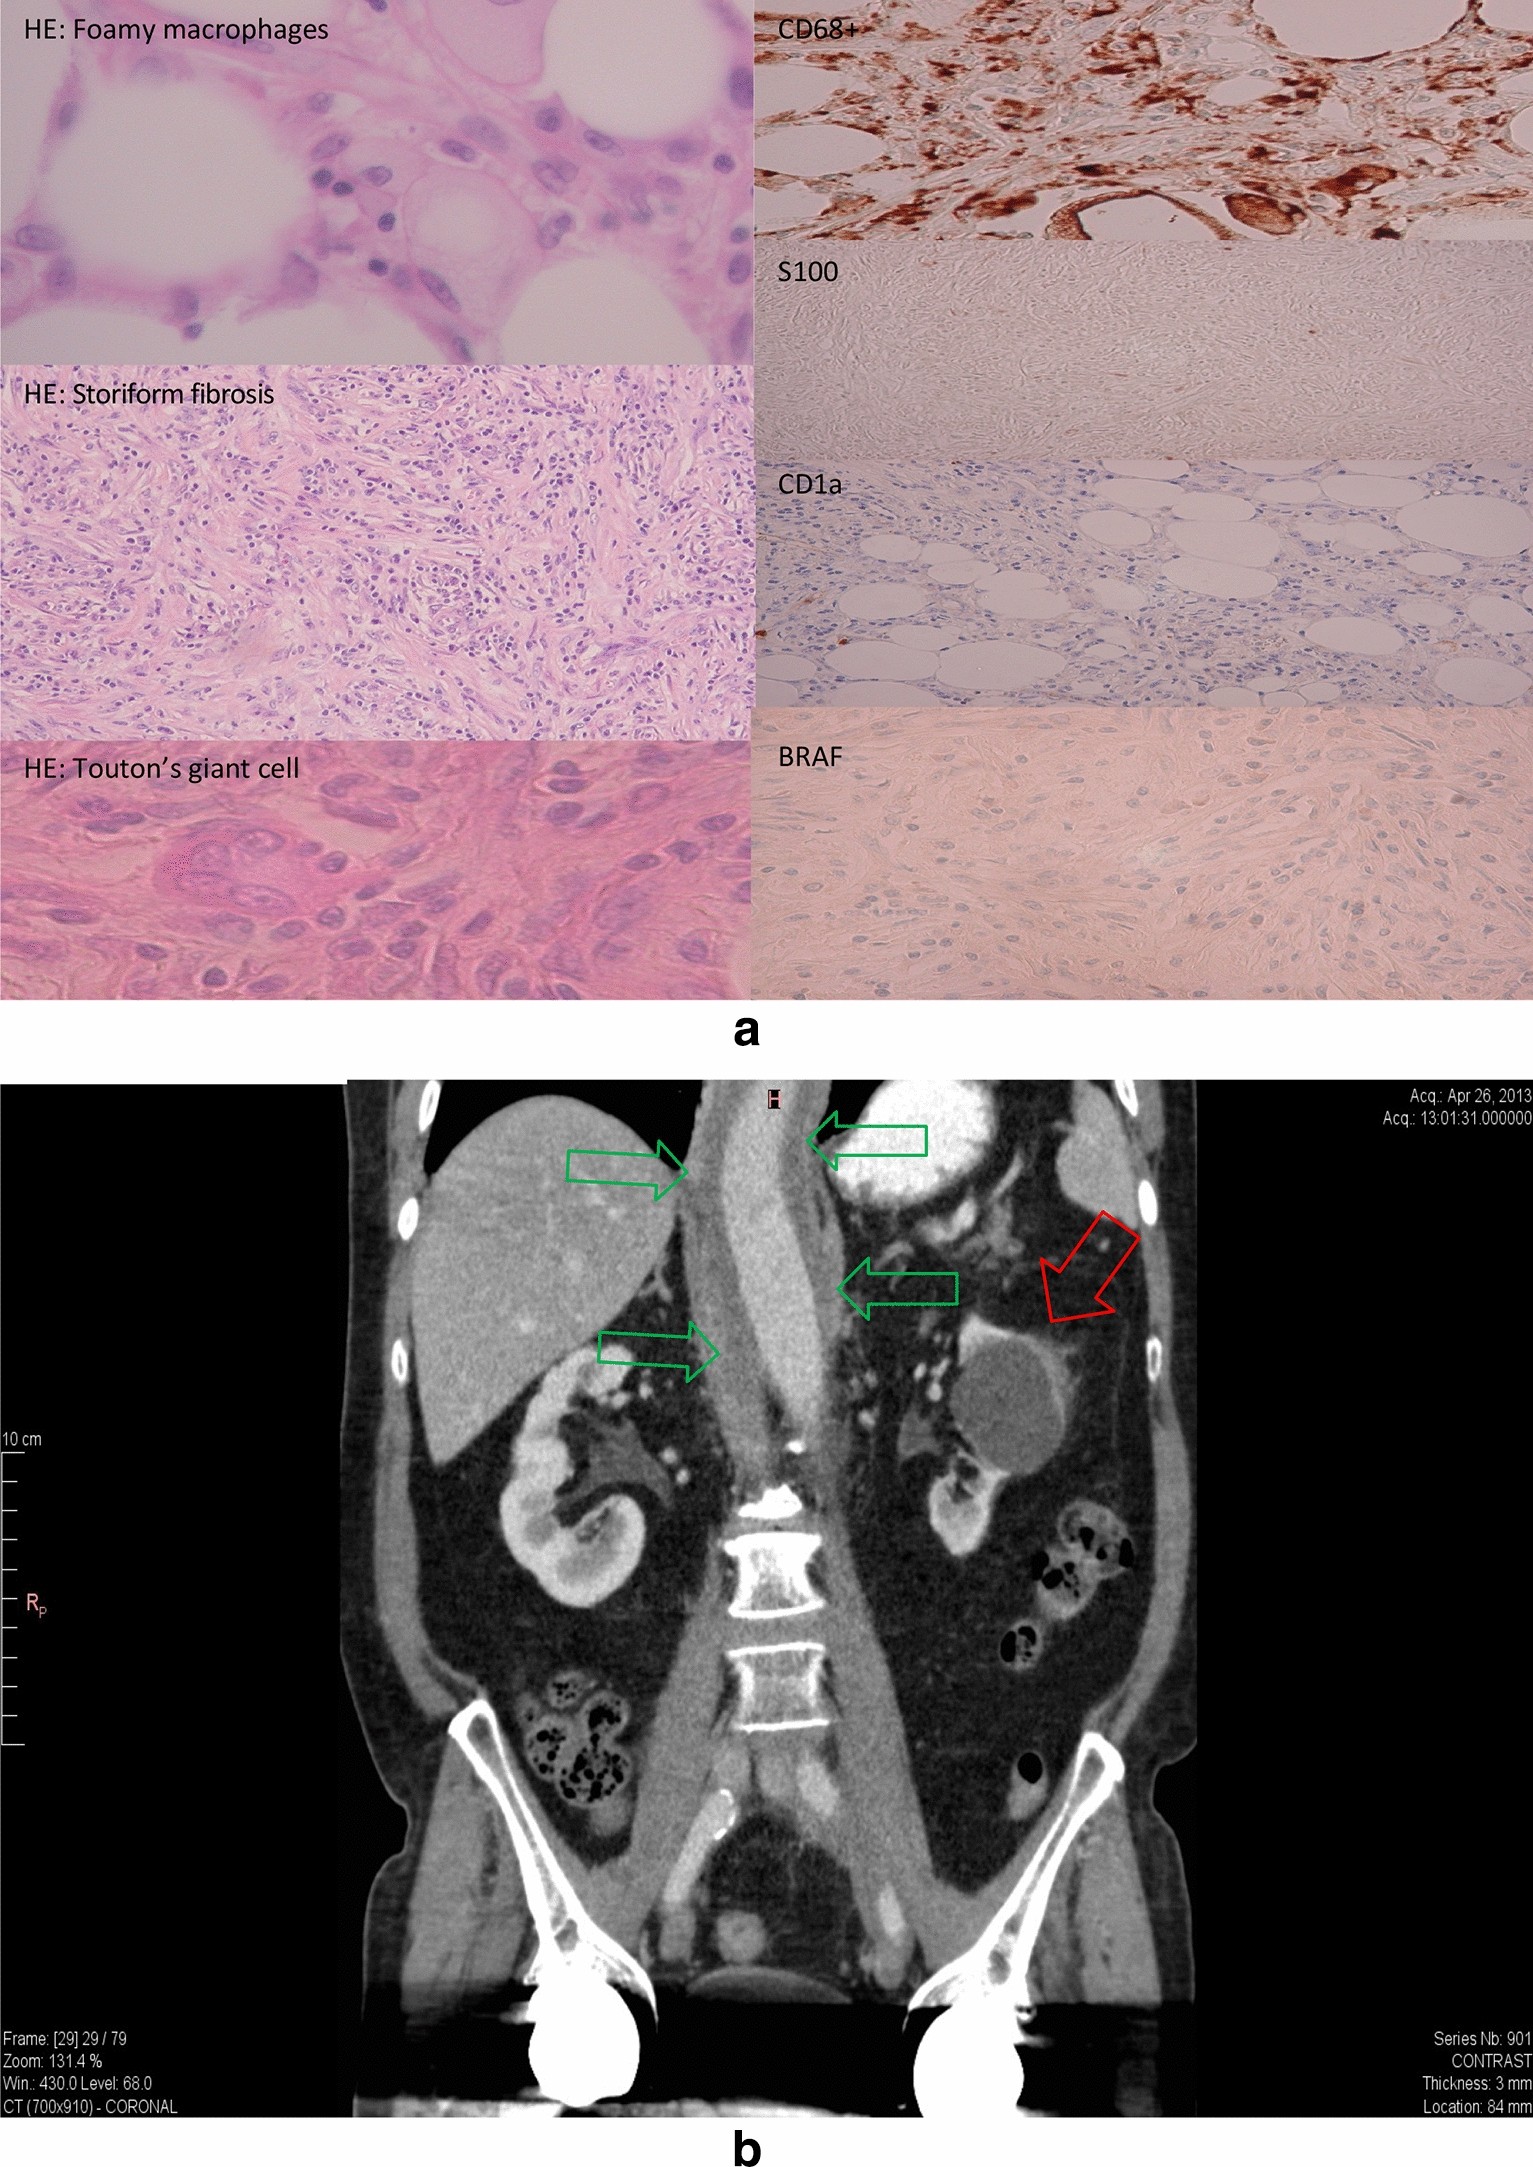

Fig. 2From: Three cases of BRAF mutation negative Erdheim-Chester disease with a challenging distinction from IgG4-related diseasea Renal mass histology of case 2: HE and relevant immunohistochemical stainings are shown. b CT scan of case 2: Red arrow indicates the renal mass, green arrows the periaortic fibrosisBack to article page